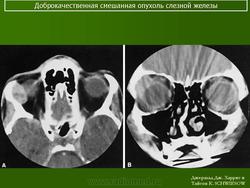

При рентгенографии выявляют увеличение полости орбиты вследствие истончения и смещения кверху и кнаружи ее стенки в области слезной ямки. Ультразвуковое сканирование позволяет определить тень плотной опухоли, окруженной капсулой, и деформацию глаза. При компьютерной томографии опухоль визуализируется более четко, можно проследить целость капсулы, распространенность опухоли в орбите, состояние ее прилежащих костных стенок. Лечение только хирургическое. Прогноз для жизни и зрения в большинстве случаев благоприятный, но пациента следует предупредить о возможности рецидива, который может возникнуть через 3—45 лет. Приблизительно у 57 % больных при первом же рецидиве обнаруживают элементы озлокачествления. Опасность злокачественного перерождения плеоморфной аденомы возрастает по мере увеличения периода ремиссии.